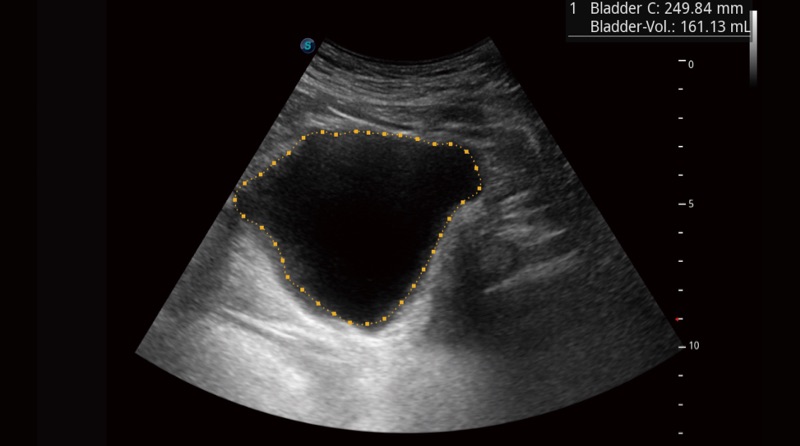

Automatinė šlapimo pūslė

„Auto Bladder“ vienu raktu sekant šlapimo pūslės sieneles ir matuojant tūrį galima efektyviai užtikrinti tikslesnį kontūrą ir rezultatus, kurie nepriklauso nuo šlapimo pūslės formos ir dydžio.